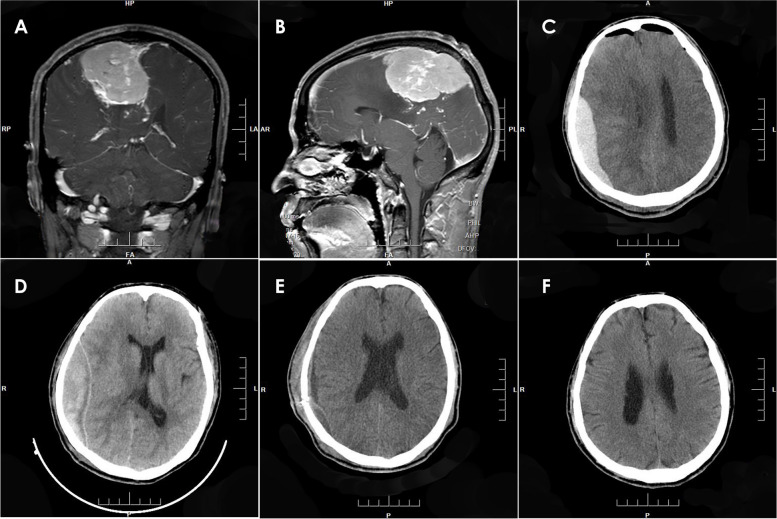

Results: Twenty-five patients (10 males, 15 females; median age 42 years, range 11-61 years; median medical history 27 months, range 1-96 months) were enrolled in the study. Regarding tumor location, 16 cases exhibited supratentorial brain tumors, 4 cases had infratentorial brain tumors, 2 cases of tumors occurred in the petroclival region, 2 cases in the peritorcular region, and 1 case in the pineal region. Four of these cases were complicated with supratentorial hydrocephalus. The 25 cases in this study were classified into four types based on location. Type 1 refers to EDHs that occur at the adjacent site of the operative field without involvement of the surgical area. Type 2 includes hematomas that occur at the adjacent site of the surgical area and the surgical area. Type 3 includes EDHs that occur in distant areas, and type 4 involves EDHs in the surgical field. The numbers of cases of types 1, 2, 3, and 4 PEDHs were 16, 2, 3, and 4 cases, respectively. Most PEDHs were associated with reduced ICP after craniotomy due to intracranial tumor resection and substantial loss of CSF. All patients achieved satisfactory outcomes after hematoma evacuation.